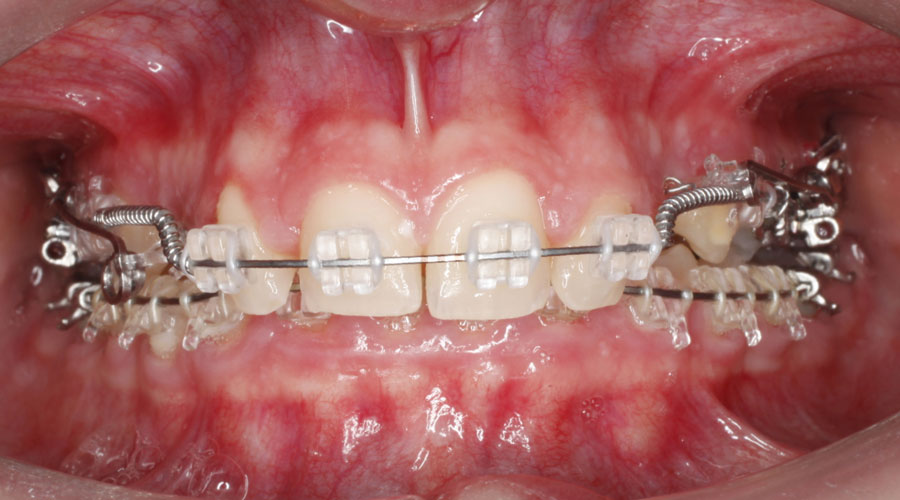

Caso clínico 2. La paciente presentaba Clase II dentaria división 2ª, con gran sobremordida, además de erupción ectópica de los caninos superiores. Se realizó ortodoncia multibracket transparentes con cirugía de fenestración de ambos caninos. Debido a la posición de éstos por palatino, colocamos dos microtornillos para ayudarnos en su tracción y poder separar la corona de las raíces de los incisivos. Posteriormente, traccionamos desde la cara vestibular con ayuda de un resorte para colocarlo en su lugar en la arcada.